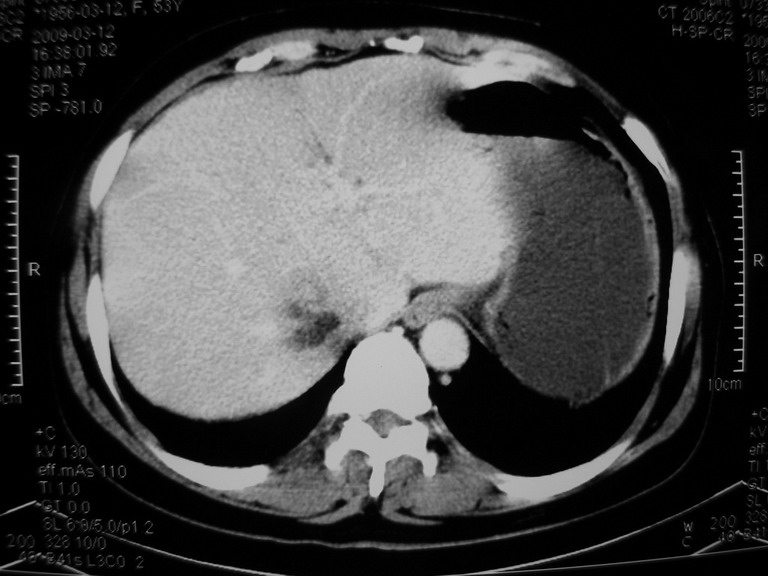

患者,女性50岁,上腹部不适2年余,既往多次腹部彩超未见异常,今日上午在我院查彩超发现肝右叶囊实性病变,外院辅助检查,afp,cea,ca199, 都在正常范围内,无肝炎史否认肿瘤史,生活在牧区

接着往下一贴看,有静脉期和延迟期,在看看和下腔静脉及十二指肠的关系,腔静脉内是不是栓子?